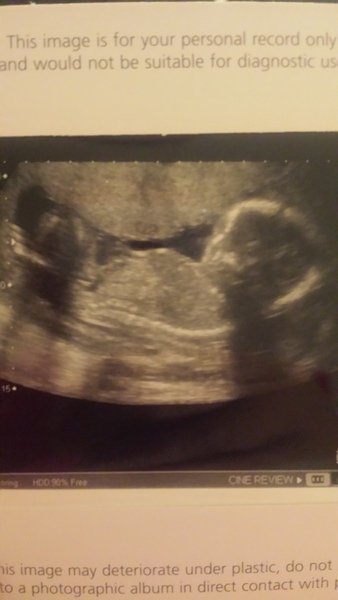

This is my scan pic (well i got 5) i have an anterior placenta but its not low. Anyone know if i should be having another scan later in pregnancy? Im having a c section so im worried incase the surgeon cuts through it

Here you are theone

Btw theone that was me at 20+2. The sonographer implied that i did well to get that so early but I had thought going much later, things would be a bit squishy. Maybe worth confirming the best time to go for one if you're paying.

Wow, gorgeous scan pictures M33r and Life! Grin